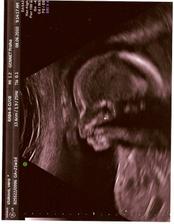

Naše princezna

20tt budeme mít HOLČIČKU!!!!!

Tak nám to u všech vyšlo i teď ta holčička,potvrdily nám to i na 3 ultrazvukách,tak doufám že to tak bude 🙂))